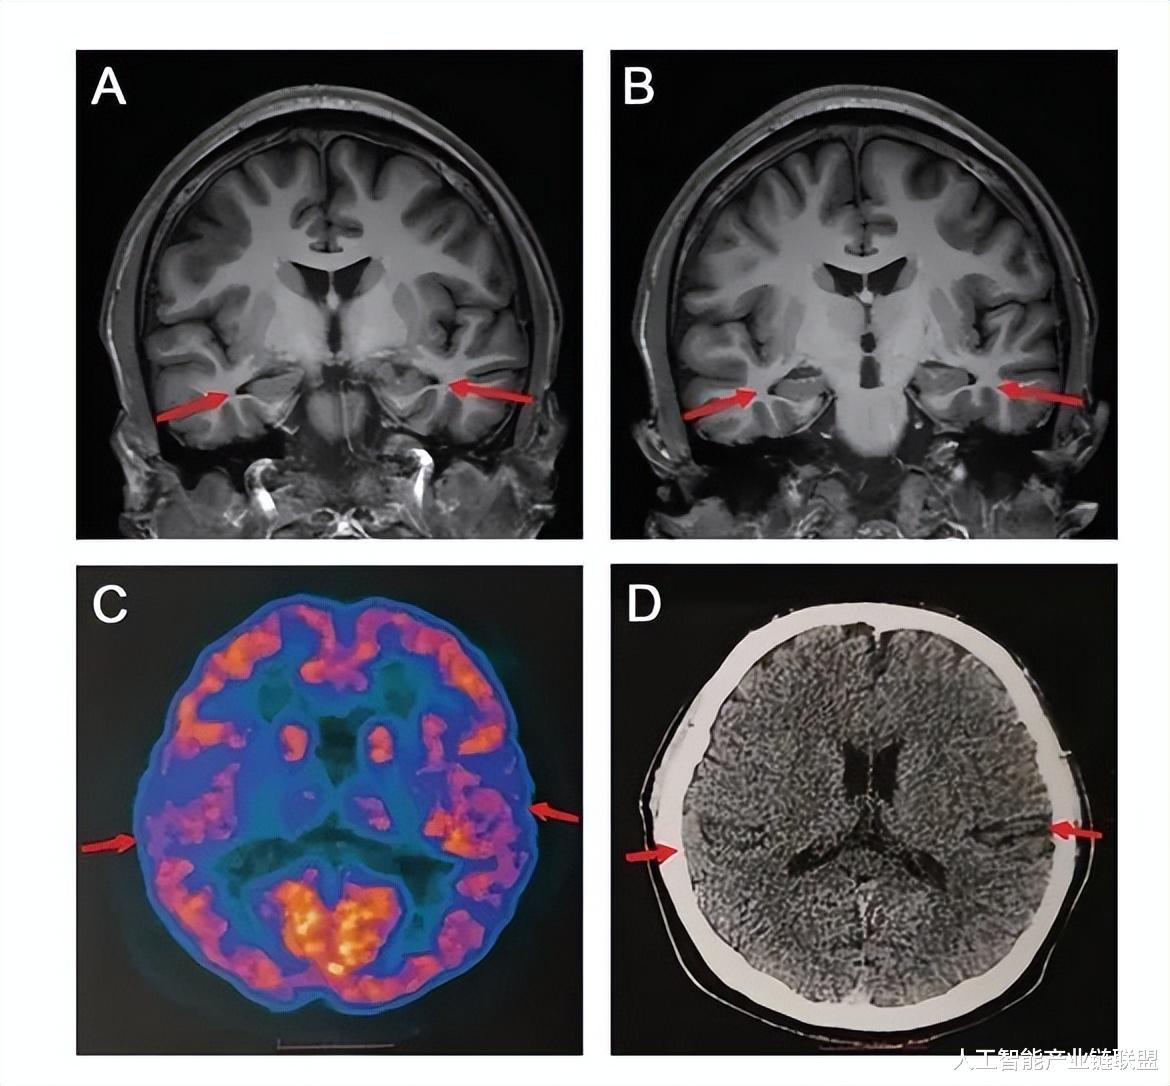

3、医生发现 19 岁阿尔兹海默症患者:已知最年轻

近日消息 , 据北青网报道 , 一篇由首都医科大学宣武医院贾建平团队撰写的论文 , 发布在了国际知名阿尔兹海默病研究刊物上 , 文中介绍 , 一名来医院就诊的 19 岁男孩被临床诊断为阿尔兹海默症患者 , 而他也是目前已知的最年轻的患者 。

据了解 , 该男子因为记忆衰退而到医院求医 , 他的病情很严重 , 无法记起头一天发生的事 , 又或者忘记自己的物品放在哪里 , 甚至会忘记有没有吃东西 , 由于病情严重 , 不得已而退学 。